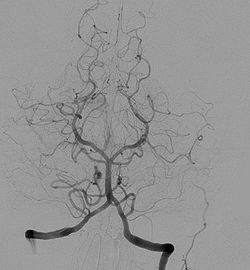

La insuficiencia vertebrobasilar es una condición clínica que se caracteriza por una disminución del flujo sanguíneo en el sistema arterial vertebrobasilar, el cual está compuesto por las arterias vertebrales y la arteria basilar. Este sistema arterial es fundamental ya que provee sangre al tronco cerebral, el cerebelo y el bulbo raquídeo, regiones del cerebro que desempeñan un papel crucial en el mantenimiento del equilibrio y la coordinación.

La arteriosclerosis, la presión arterial elevada y otras condiciones que afectan la elasticidad y el diámetro de las arterias pueden contribuir a la reducción del flujo sanguíneo en el sistema vertebrobasilar. Estos cambios pueden ser evaluados de manera no invasiva mediante la angiografía por resonancia magnética (MRA), que permite visualizar y cuantificar la circulación sanguínea en estas arterias.